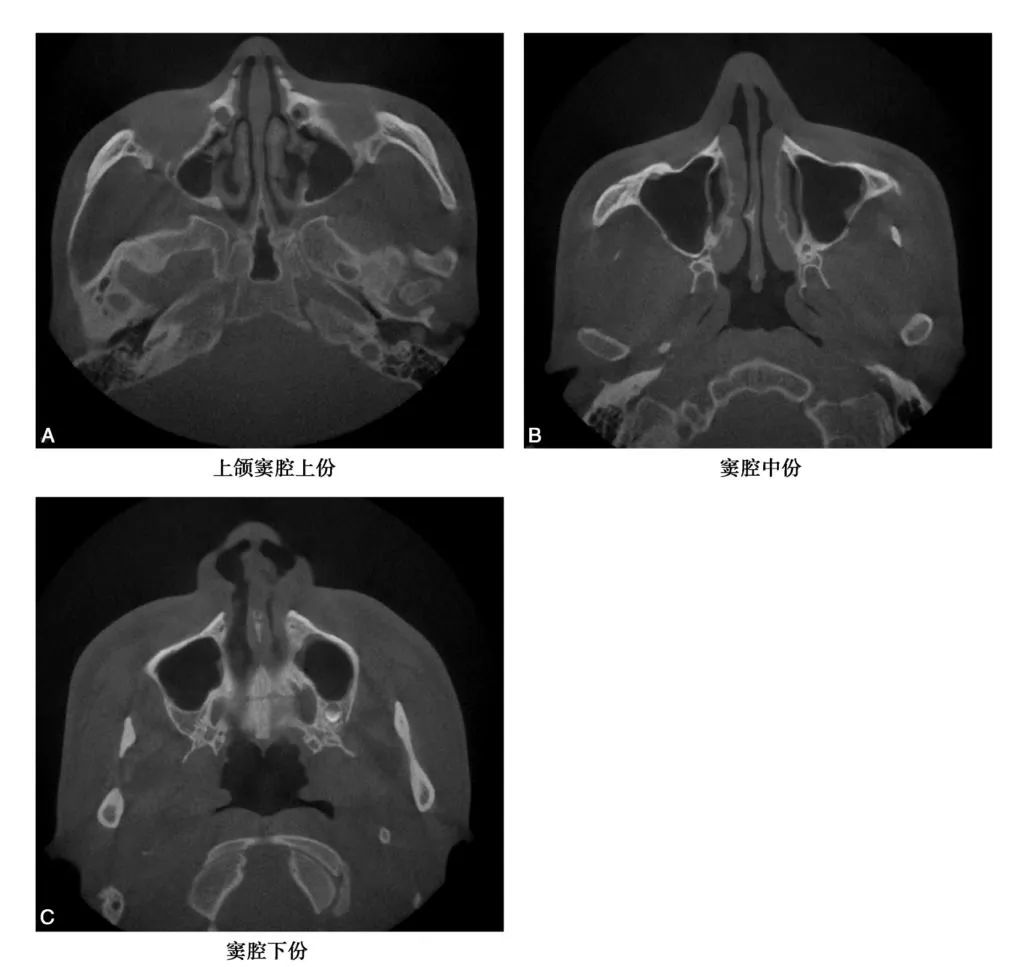

CBCT图像显示上颌窦是一个形状不规则,大小也不尽相同的腔,矢状位上是一由上、下、前、后壁构成的类似四方形或者梯形结构(图1-1-12)。冠状位上可见上颌窦上、下、内、外壁,形态多不规则(图1-1-13)。水平位可见前外、后外、内壁,中份多为类三角形,两端形态多不规则(图1-1-14)。上颌窦腔的容积为9. 5~20ml,平均为14. 75ml。不同人上颌窦形状和大小差别较大,同一个体双侧上颌窦形态基本对称(图1-1-15),但也存在同一个体两侧上颌窦形状和大小有差异(图1-1-16)。

A、C.可见窦腔形态不规则; B.窦腔形态类似三角形